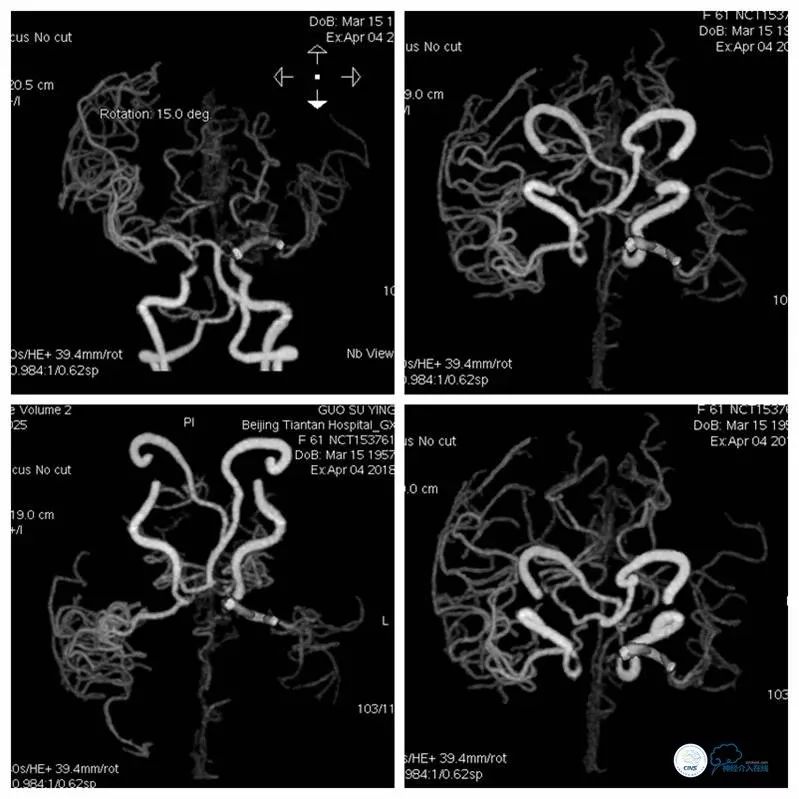

CTA+CTP(2018-4-4):左大脑中动脉支架术后,远端血管分支较对侧减少。左侧半球低灌注,间接提示左大脑中动脉支架术后再狭窄可能(图4,5)。

图4

图5